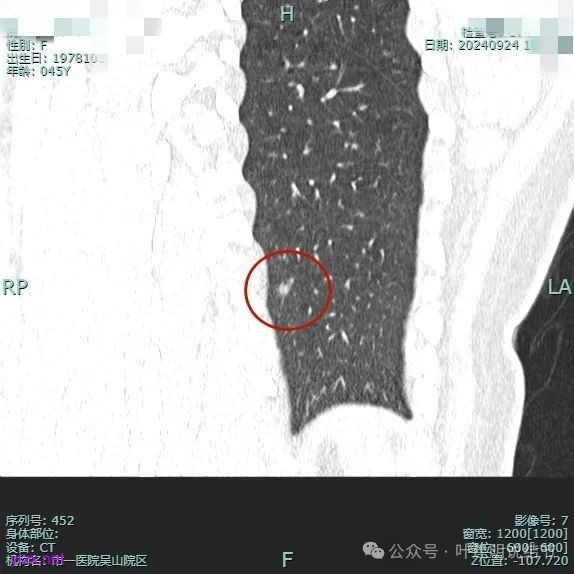

病灶1:

右下背段混合密度病灶,边上不太清爽,有片状淡磨玻璃影,实性部分密度较高。

感觉病灶有点晕征似的,表面不平,灶内不太致密。

有小血管进入,似有晕征。

离胸膜近但牵拉不明显,病灶边缘有细毛刺,较短且不太锐利。

边缘少许磨玻璃成分,血管进入明显。

瘤肺边界稍显不清。